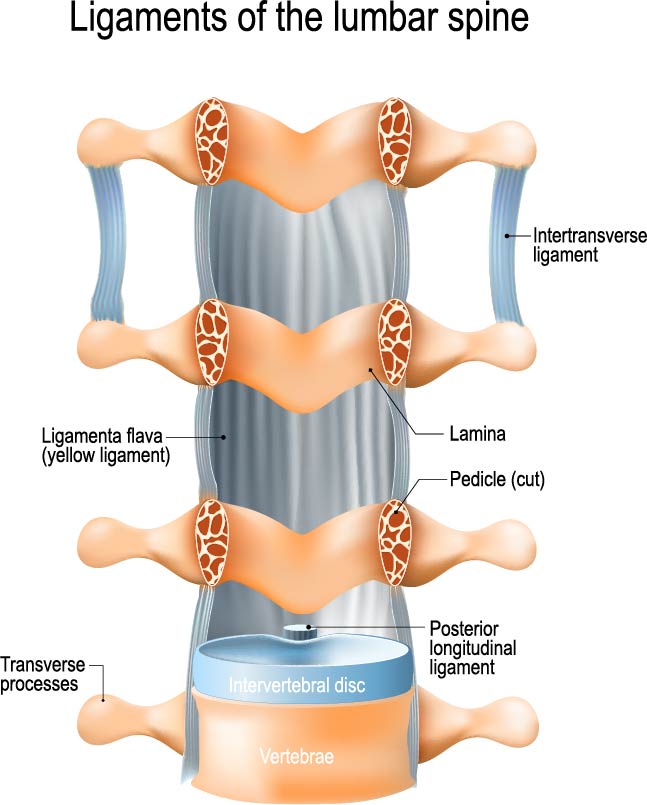

Ligaments of the Lumbar Spine

The image showcases a detailed representation of the ligaments associated with the lumbar spine, which is the lower part of the vertebral column. These ligaments are crucial for providing stability to the spine while allowing for a range of movements.

From the front to the back, we can observe the intervertebral disc, which is a fibrocartilaginous structure acting as a cushion between adjacent vertebrae. The vertebral body is not visible here, but it lies anterior to the intervertebral disc and is a major structural component of the vertebra.

The posterior longitudinal ligament runs longitudinally down the spinal column along the posterior aspect of the vertebral bodies, inside the vertebral canal. It helps to prevent hyperextension of the spine, which is excessive backward bending.

On the sides of the vertebrae, we see the transverse processes, which are small bony projections where muscles and ligaments attach. Just behind these are the laminae, part of the vertebral arch that forms the roof of the spinal canal.

The pedicle, labeled as cut in this image, is a stub of bone that connects the lamina to the vertebral body, forming the sides of the vertebral arch.

The ligamenta flava, also known as the yellow ligaments, are bands that connect the laminae of adjacent vertebrae. They are highly elastic and preserve the upright posture by helping to straighten the spine after flexing.

The intertransverse ligaments stretch between the transverse processes of adjacent vertebrae. These ligaments aid in lateral stability and prevent excessive side-to-side movements.

This diagram effectively illustrates the complexity and integration of the ligamentous structures that support the lumbar spine, highlighting their role in maintaining spinal integrity and facilitating movement.